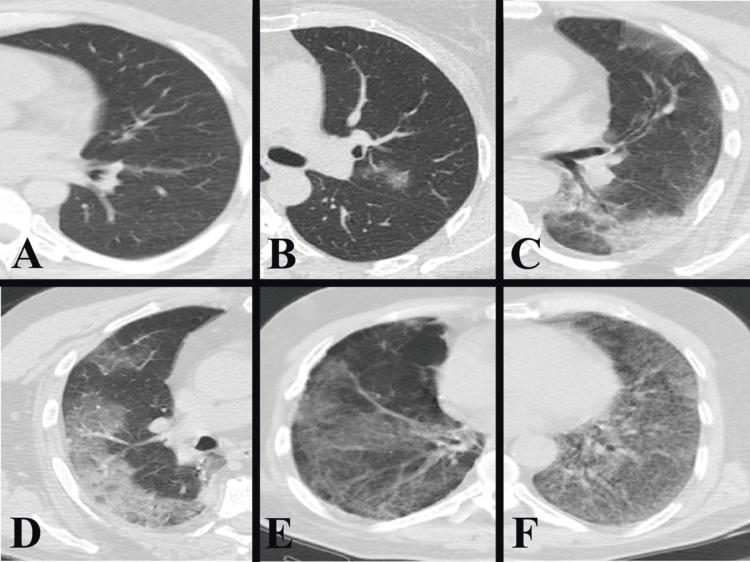

Background The COVID-19 infection has spread rapidly since its emergence and has affected a large part of the global population. With the increasing number of cases, researchers are trying to predict the prognosis of patients by using different data with artificial intelligence methods such as machine learning (ML). In this study, we aimed to predict mortality risk in COVID-19 patients using ML algorithms with different datasets. Methodology In this retrospective study, we evaluated the fever, oxygen saturation, laboratory results, thorax computed tomography (CT) findings, and comorbid diseases at admission to the hospital of 404 patients whose diagnosis was confirmed by the reverse transcription polymerase chain reaction test. Different datasets were created by combining the data. The Synthetic Minority Oversampling Technique was used to reduce the imbalance in the dataset. K-nearest neighbors, support vector machine, stochastic gradient descent, random forest, neural network, naive Bayes, logistic regression, gradient boosting, XGBoost, and AdaBoost models were used to create the ML algorithm, and the accuracy rates of mortality prediction were compared. Results When the dataset was created with CT parenchyma score, pulmonary artery and inferior vena cava diameters, and laboratory results, mortality was predicted with an accuracy of 98.4% with the gradient boosting model. Conclusions The study demonstrates that patient prognosis can be accurately predicted using simple measurements from thorax CT scans and laboratory findings.

背景 自新冠病毒病(COVID-19)感染出现以来迅速传播,已影响全球大部分人口。随着病例数增加,研究人员正尝试通过机器学习(ML)等人工智能方法利用不同数据预测患者预后。在本研究中,我们旨在使用不同数据集的ML算法预测COVID-19患者的死亡风险。方法 在这项回顾性研究中,我们评估了404例经逆转录聚合酶链反应检测确诊的患者入院时的发热、血氧饱和度、实验室检查结果、胸部计算机断层扫描(CT)结果及合并症。通过合并数据创建不同数据集。使用合成少数过采样技术减少数据集中的不平衡。使用K近邻、支持向量机、随机梯度下降、随机森林、神经网络、朴素贝叶斯、逻辑回归、梯度提升、XGBoost和AdaBoost模型创建ML算法,并比较死亡预测的准确率。结果 当使用CT实质评分、肺动脉和下腔静脉直径及实验室检查结果创建数据集时,梯度提升模型预测死亡率的准确率为98.4%。结论 该研究表明,使用胸部CT扫描的简单测量结果和实验室检查结果可准确预测患者预后。